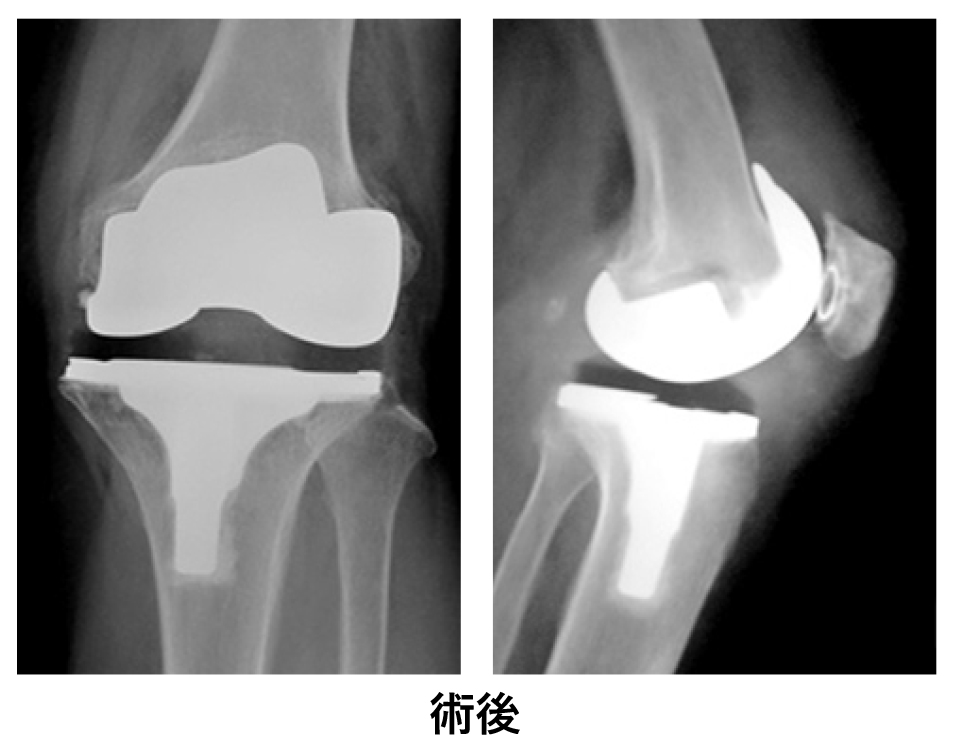

○人工膝関節全置換術と単顆膝関節置換術

膝に特殊な器具を設置します。

○写真で見る人工膝関節全置換術